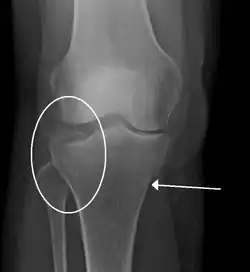

Subtle tibial plateau fracture on an AP X ray of the knee -

A tibial plateau fracture seen on X-ray